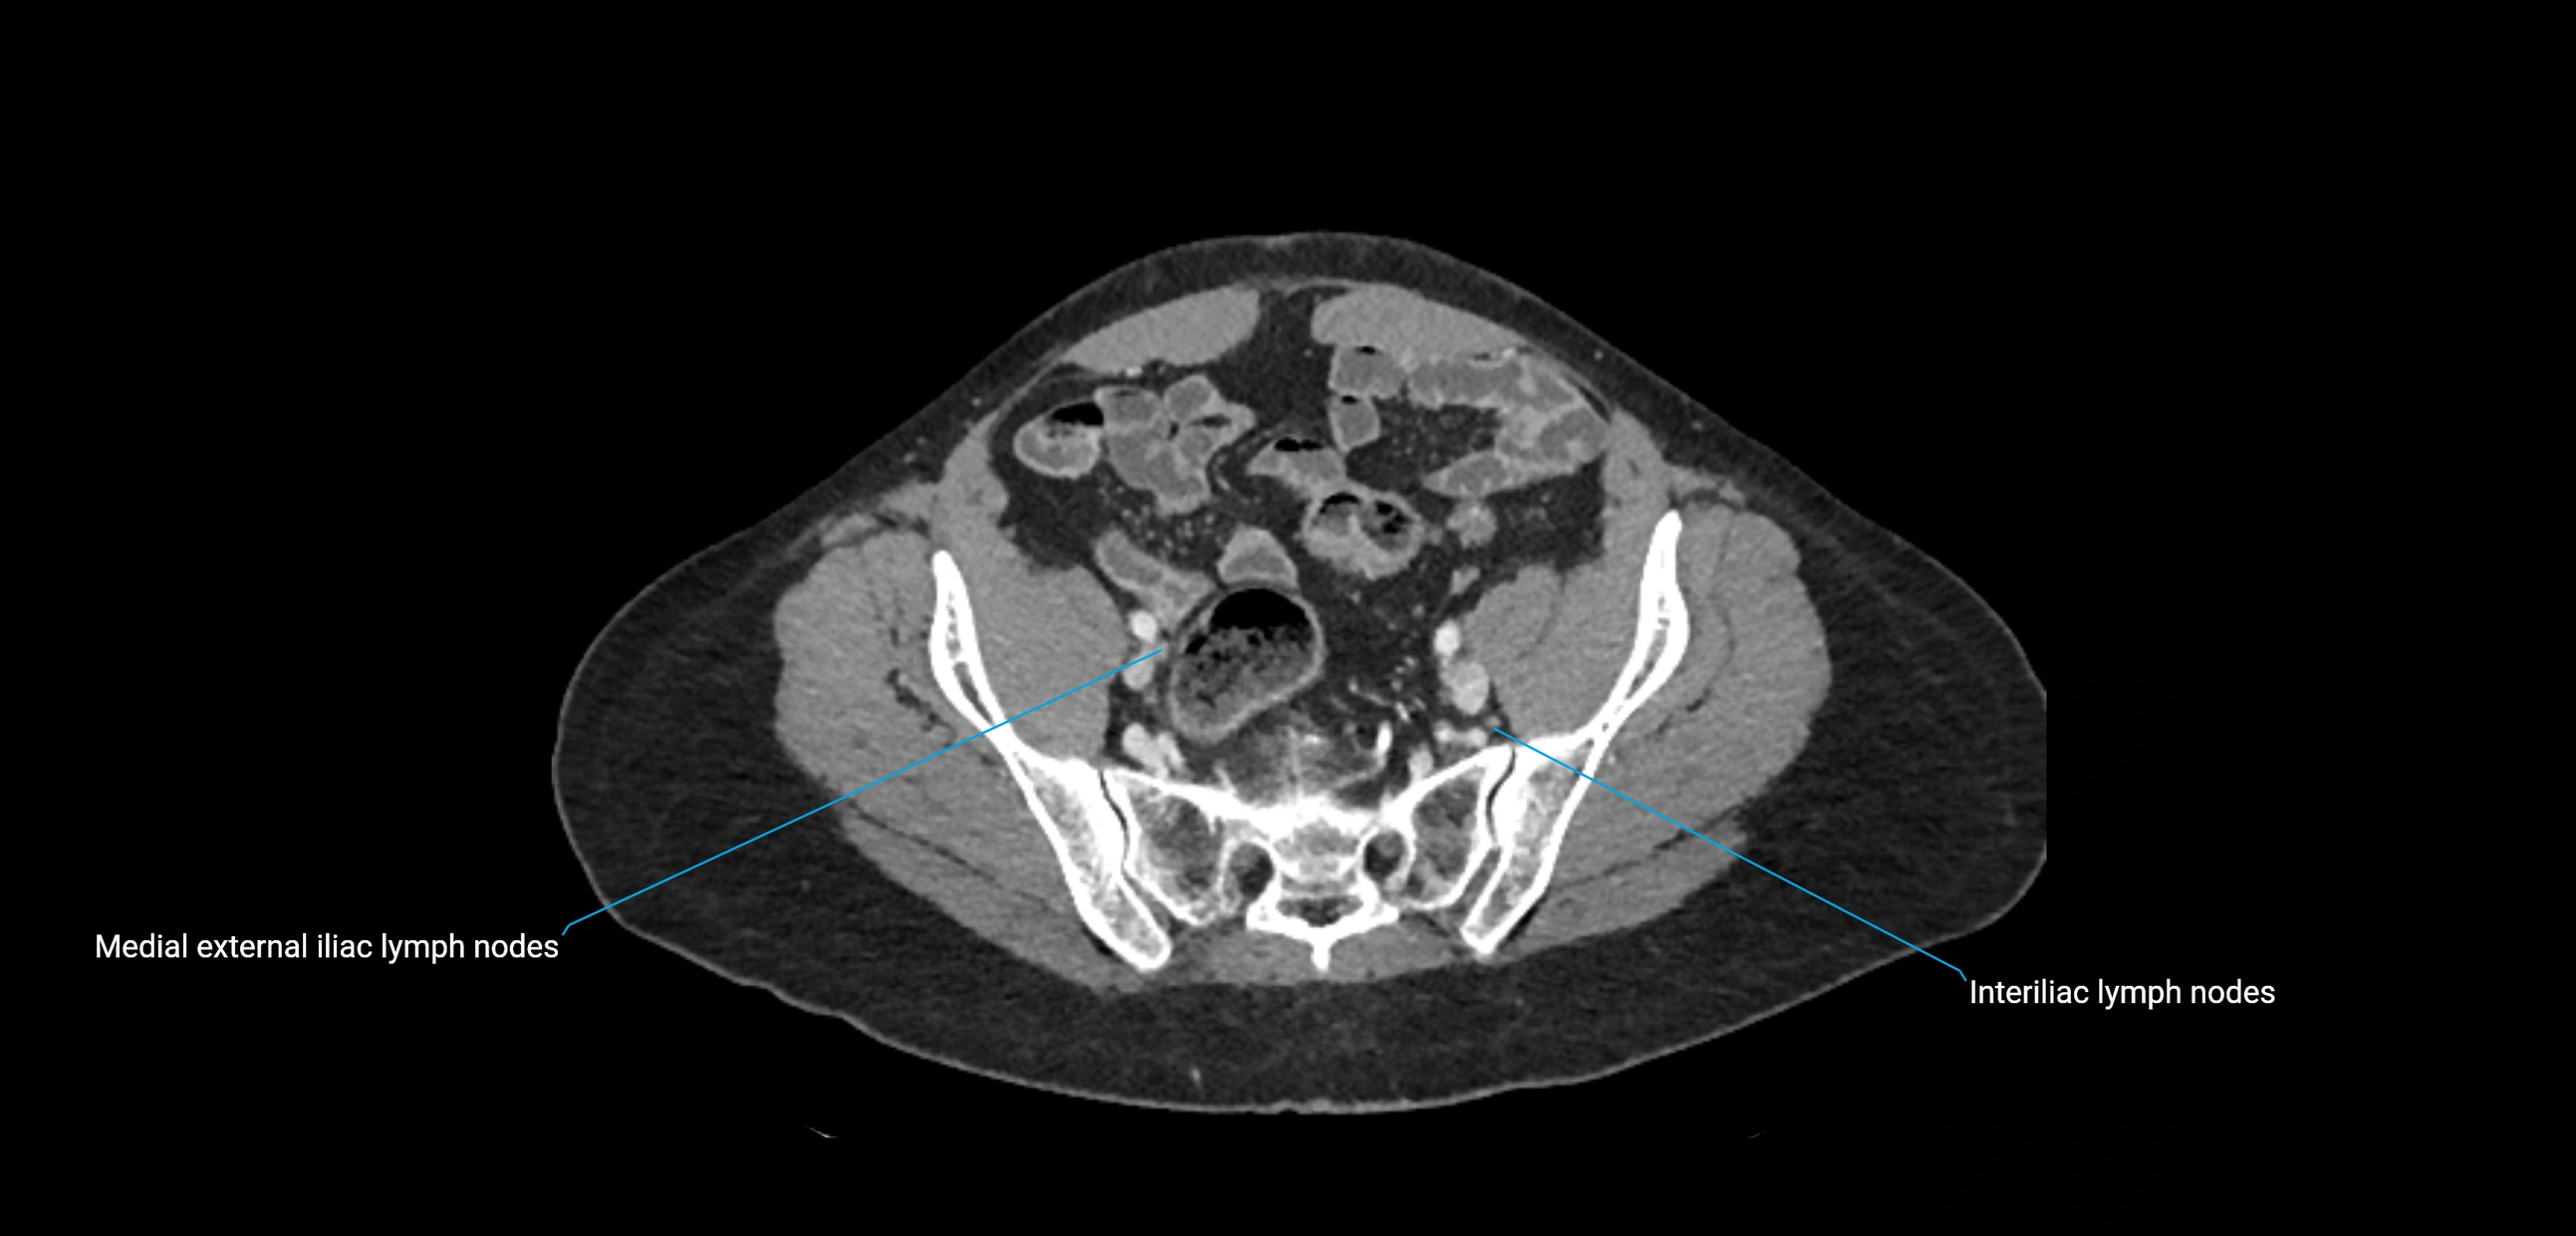

CT image

image